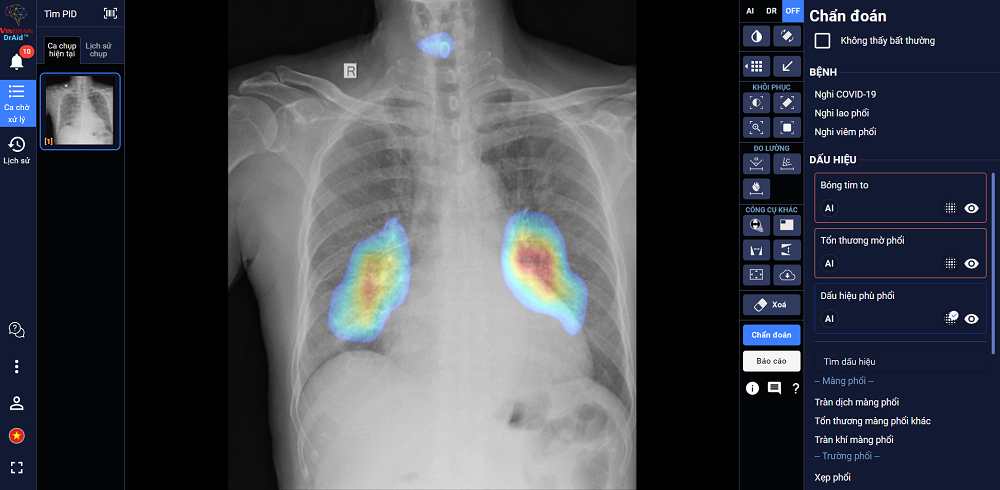

| Giao diện của ứng dụng DrAid – AI trợ lý bác sĩ đầu tiên tại Việt Nam |

Phần mềm hỗ trợ chẩn đoán 20 dấu hiệu bất thường và bệnh lý, độ chính xác trên 88%

DrAid được đào tạo dựa trên bộ dữ liệu lớn 1,3 triệu hình ảnh X-quang, trong đó hơn 326 nghìn hình ảnh được gán nhãn và bộ dữ liệu COVID-19 lớn thứ 2 toàn cầu với 7.592 hình ảnh dương tính của bệnh nhân COVID-19. Hiện DrAid có khả năng hỗ trợ chẩn đoán 20 dấu hiệu bất thường và bệnh lý về Tim – Phổi – Xương dựa trên hình ảnh X-quang ngực với độ chính xác trên 88% trong vòng 5 giây, đồng thời tự động đưa ra báo cáo y tế theo chuẩn quốc tế JCI có khoanh vùng và đo kích thước chính xác tại khu vực bất thường.